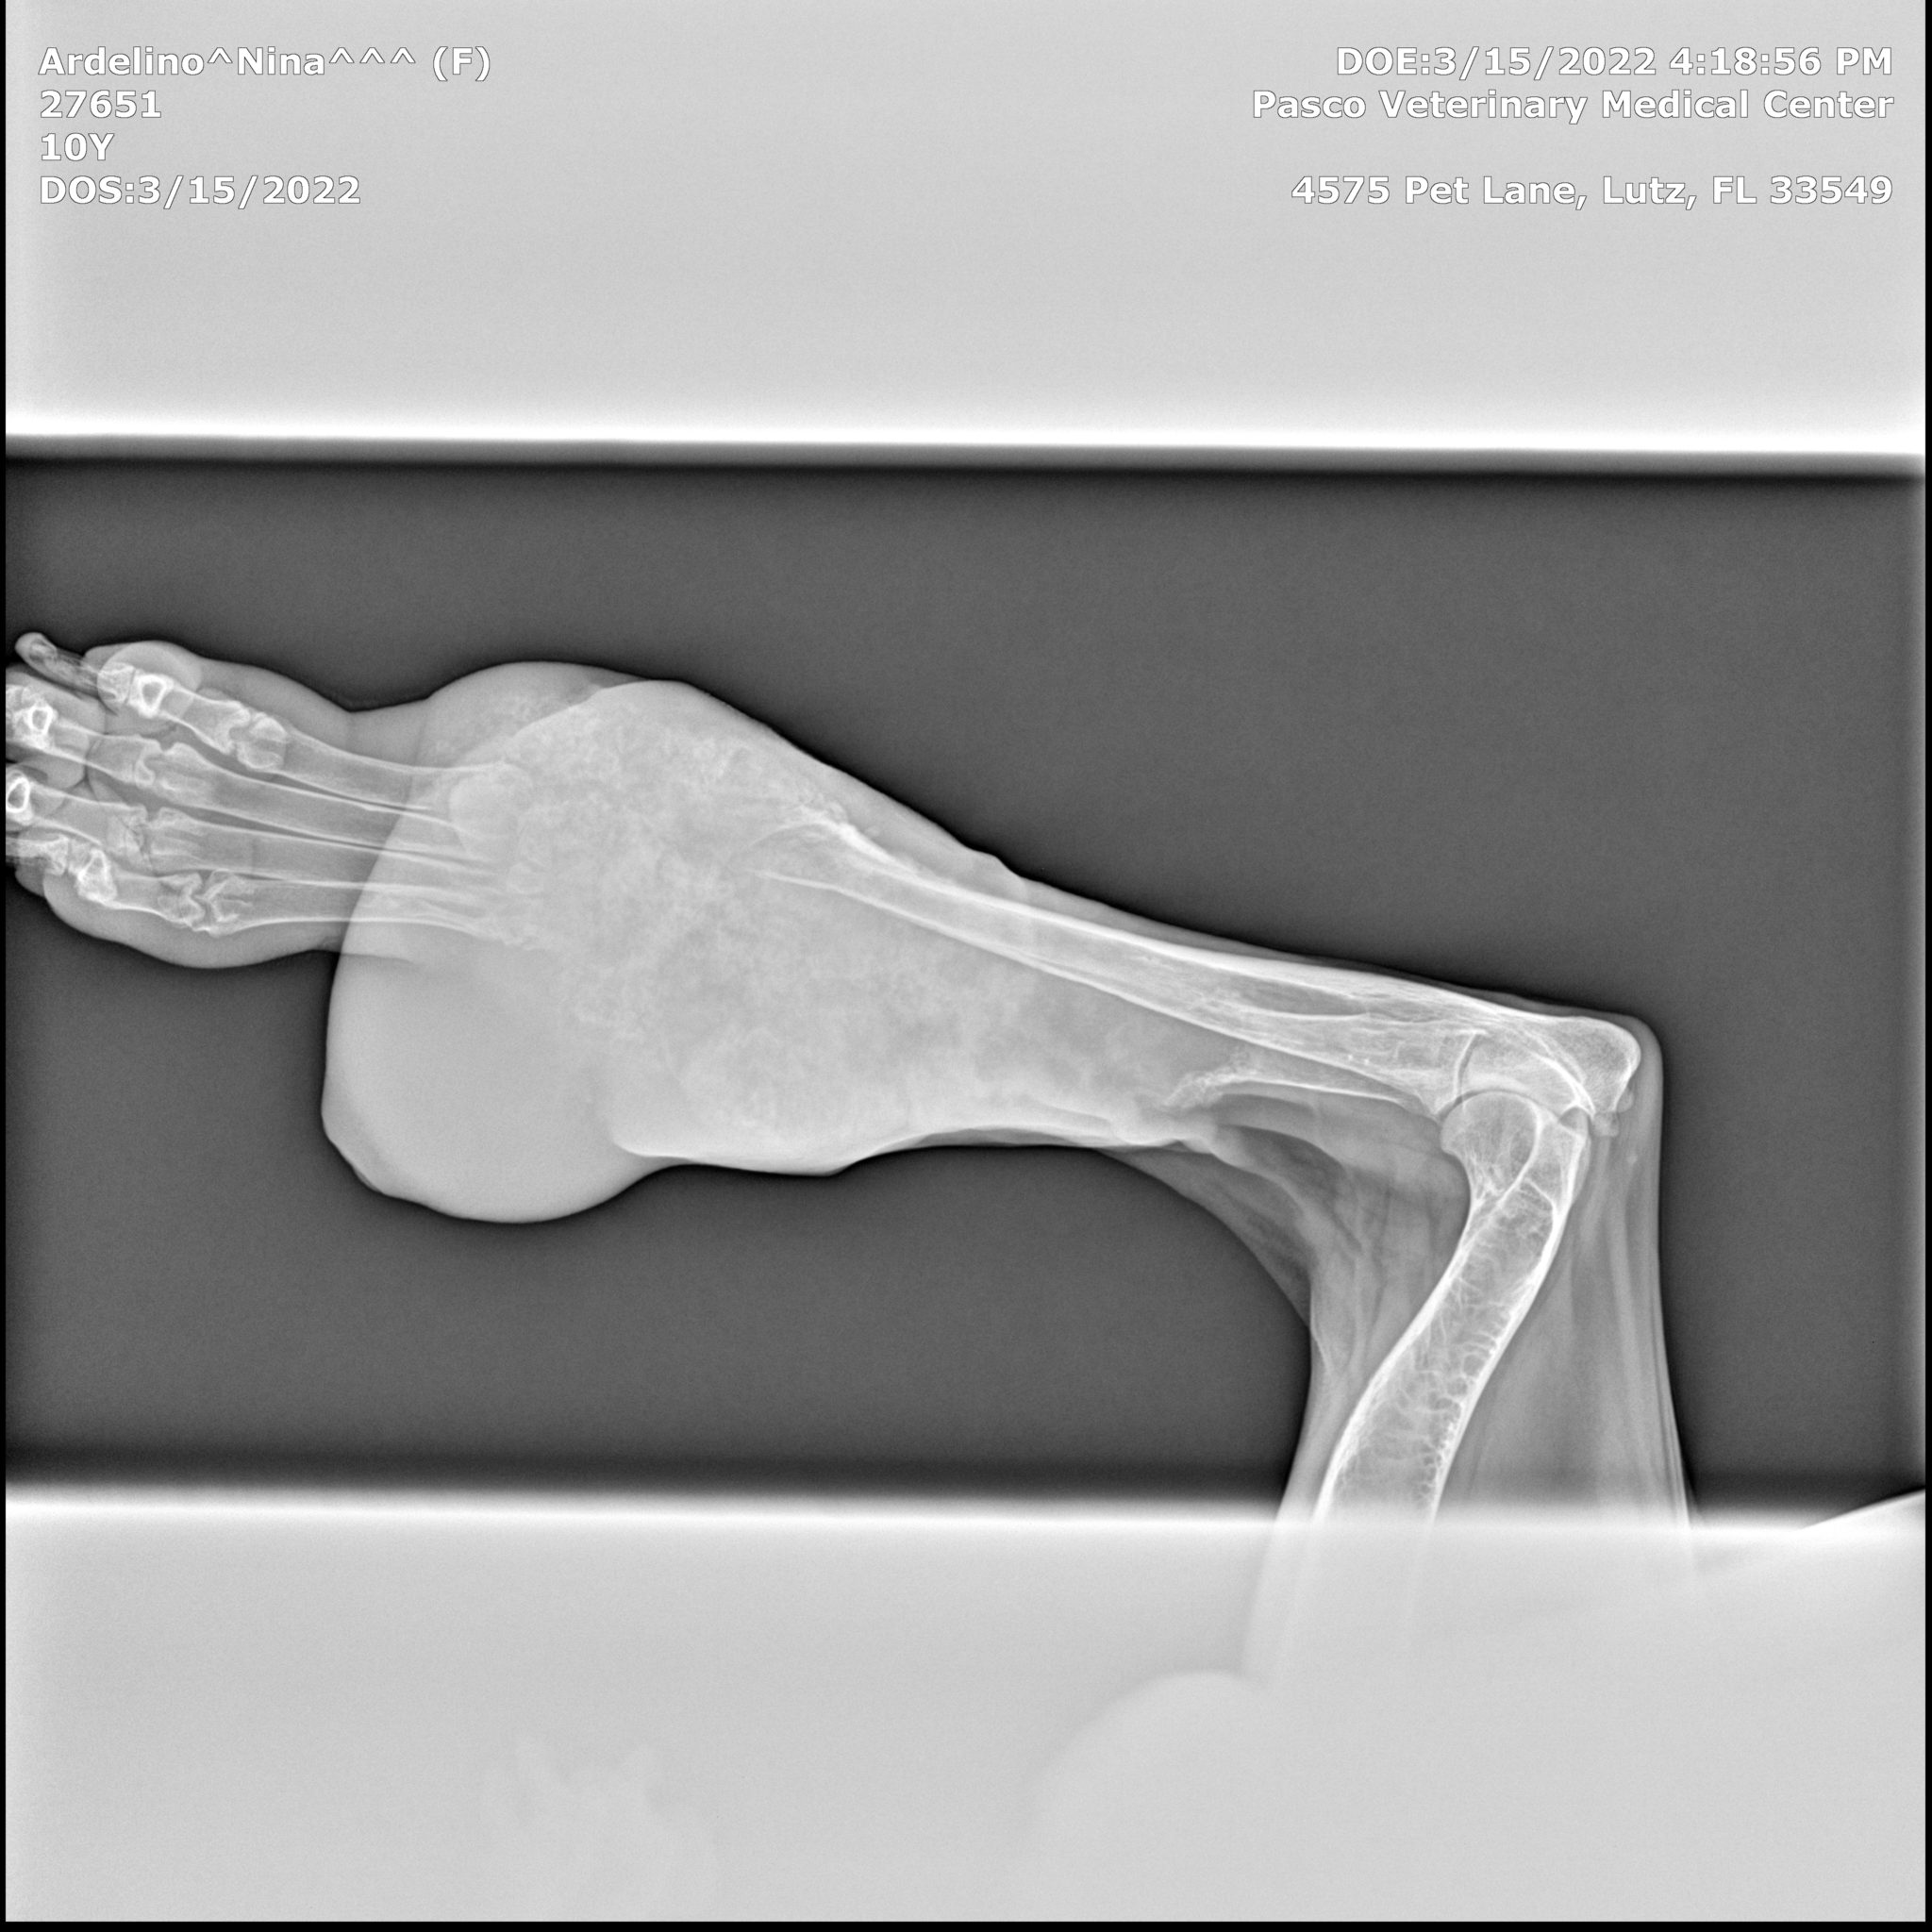

The tumor had grown to the size of a grapefruit, and was cutting off circulation to her foot. It had also started to seep fluids, through a small sore on the surface of the growth. This meant that we would once again run all the diagnostic tests again to see if, after 22 months, the cancer had metastasized.

Here are Nina’s X-rays, showing no metastasis, no spread of cancer 22 months post diagnosis of osteosarcoma in dogs:

In my previous update, one year post diagnosis, Nina was not a good candidate for amputation. But this year however, circumstances had changed. By March 17th, 2022, (22 months post osteosarcoma diagnosis), we knew it was time for Nina’s leg to be amputated.

“It’s remarkable that Nina’s tumor has stayed localized to her wrist and still hasn’t spread after 22 months, I’ve never seen anything like this and it helps me understand the power of cannabis, and adaptogens.”